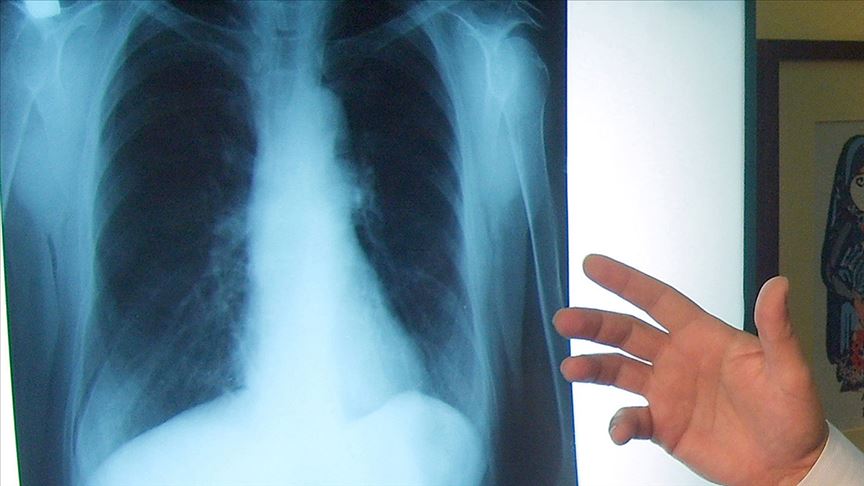

Kombine Tedaviyle Akciğer Kanserinde Umut Veren Gelişme: Yaşam Süresi 1,5 Kat Uzadı

Metastatik küçük hücreli dışı akciğer kanserinde, Nivolumab ve Ipilimumab kombinasyonu hastaların yaşam süresini 1,5 kata kadar uzattı. Medical Park Seyhan Hastanesi Tıbbi Onkoloji Uzmanı Prof. Dr. Ahmet Taner Sümbül, bu tedavi yaklaşımının hastalığın ilerlemesini anlamlı ölçüde azalttığını ve artık SGK kapsamında erişilebilir hale geldiğini açıkladı.

Dünyada her yıl yaklaşık 2,2 milyon kişinin akciğer kanseri tanısı aldığını belirten Prof. Dr. Sümbül, Türkiye’de de bu hastalığın erkeklerde en sık, kadınlarda ise ikinci en sık görülen kanser türü olduğunu ifade etti. Sigara, hava kirliliği ve genetik faktörlerin en önemli risk unsurları arasında yer aldığını söyleyen Sümbül, erken tanı oranlarının düşüklüğü nedeniyle hastaların büyük kısmının ileri evrede teşhis edildiğini vurguladı.